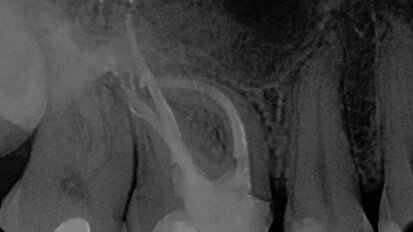

Endodontics made more efficient with the ScanX Swift

Technology has made endodontic treatment faster and more efficient. However, there are still parts of the endodontic protocol that cannot be avoided that ...